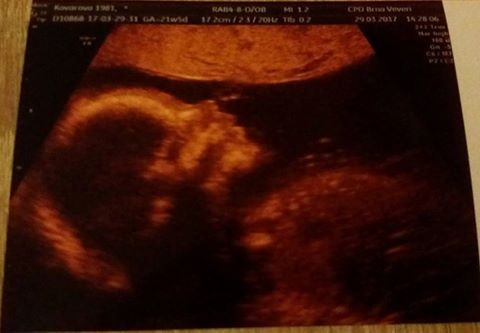

Tak včerejší utz ok. Všechno co prohlížel, vypadá v pořádku a prcek se sice zase moc ukazovat nechtěl, pořád si dával ruce před obličej a nohy křížem, ale dr. si ho různě natáčel a odhalil holku!

?miminko je v pořádku, roste pěkně a podle slov pana doktora je to pěkný kousek a žádný dvoukilovy chudaček to prý nebude...je skoro o týden větší než podle ms... a je to tedy opravdu holčička

Krj to jste byli u toho Vlasina? Jak jsi byla tentokrat spokojena? A to sis to pohlavi nakonec nechala rict? Jinak krasna fotka a gratulace k dobrym zpravam ;-)